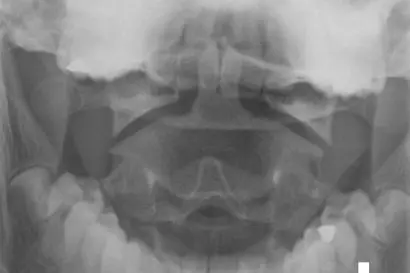

Dersom rtg.cervicalcolumna er indisert, skal det tas front og sidebilde, samt frontbilde av dens axis med åpen munn hvis mulig.

Frontbilde av dens axis